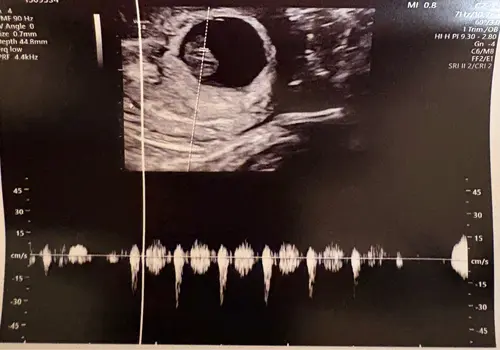

Heb je nog meer echo foto鈥檚, bij deze is het lastig te zien. Gaat er om hoe je kleine geloof ik in het vruchtzakje zit.

Deze beter misschien?